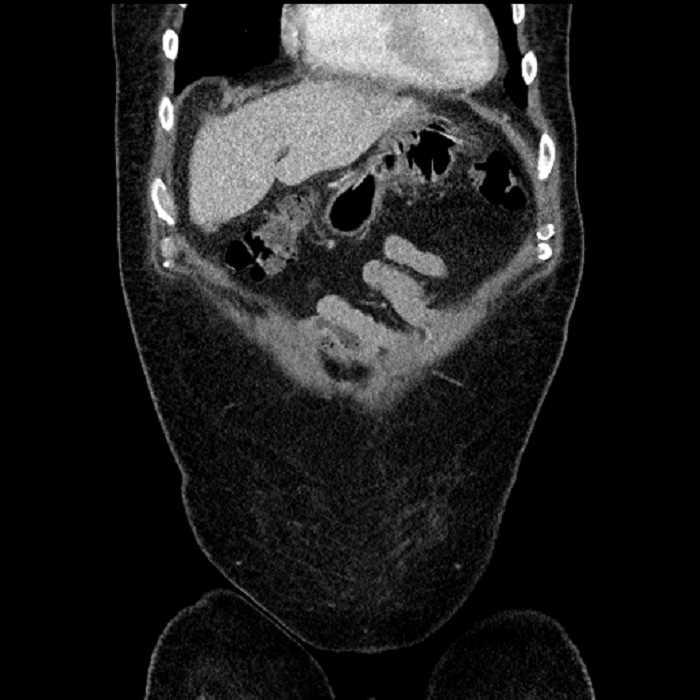

• Large fluid density structure in hepatic segments 7 and 8 measuring 10 x 7 x 7 cm with internal septation and circumferential ill-defined low density compatible with edema

• Peripherally enhancing subcapsular collections along the anterior margin of the left hepatic lobe measuring 3 x 1 cm and 2 x 1 cm

• Clearly marginated fluid density structure in segment 7 and several other scattered tiny hypodensities, which likely represent cysts

• Hepatic abscess

Acute sigmoid diverticulitis complicated by a small contained perforation and a large abscess in the right hepatic lobe. Additional small subcapsular abscesses along the anterior margin of the left hepatic lobe.

• The classic CT imaging appearance is a double target sign with internal low density surrounded by an internal enhancing rim (capsule) and a low density external rim (edema)

• Abscesses may be unilocular or multilocular

• Gas is present in a minority of cases

Hepatic abscess showing the double target sign with low density internally surrounded by a thin inner enhancing rim (red arrow) and ill-defined outer low density rim (yellow arrow). Blue arrow indicates an internal septation. Red arrows: additional smaller subcapsular abscesses. Red arrow: focal contained perforation associated with diverticulitis.